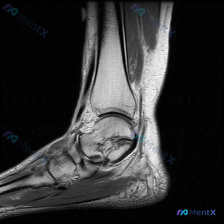

看到这个踝关节MRI的病例,整理了完整的影像资料和分析思路,和大家分享讨论。 病例影像基础信息 这是踝关节MRI T2加权轴位图像,扫描层面为踝关节远端,可见距骨体及周围软组织结构,图像对比度满足观察要求,T2加权像液体呈高信号。 核心影像发现 1. 骨结构:距骨及周围骨性结构骨髓无异常高信号,骨皮...

刚看到这份踝关节MRI读片需求,整理了完整的观察和分析思路分享给大家。 病例基本影像信息 本次读片基于踝关节MRI-T2序列轴位图像,扫描层面为踝关节远端轴位,可清晰辨认胫骨、腓骨、距骨以及后方跟腱等正常解剖结构。T2序列对液体和水肿敏感,正常肌腱韧带应为低信号(黑色),液体/水肿为高信号(白色)。...